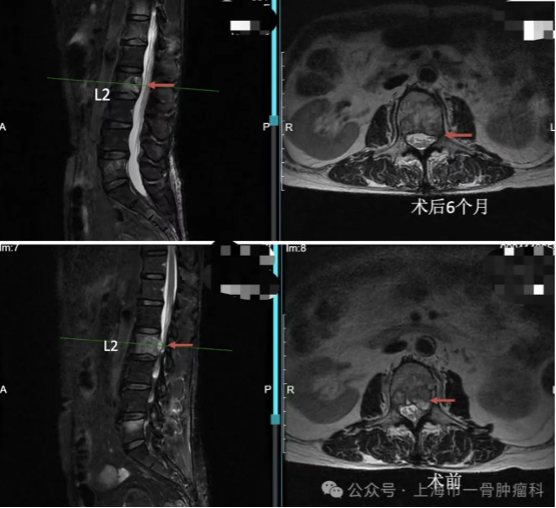

读片:CT及MRI检查提示,T2,L2,L5椎体骨质破坏,红色箭头所指为转移病灶所在位置,可见L2椎体病灶已侵犯后壁,突入椎管内。

术后6月与术前MRI对比,红色箭头处可见术后6月椎体内肿瘤较术前明显缩小,突入椎管内情况有明显好转。